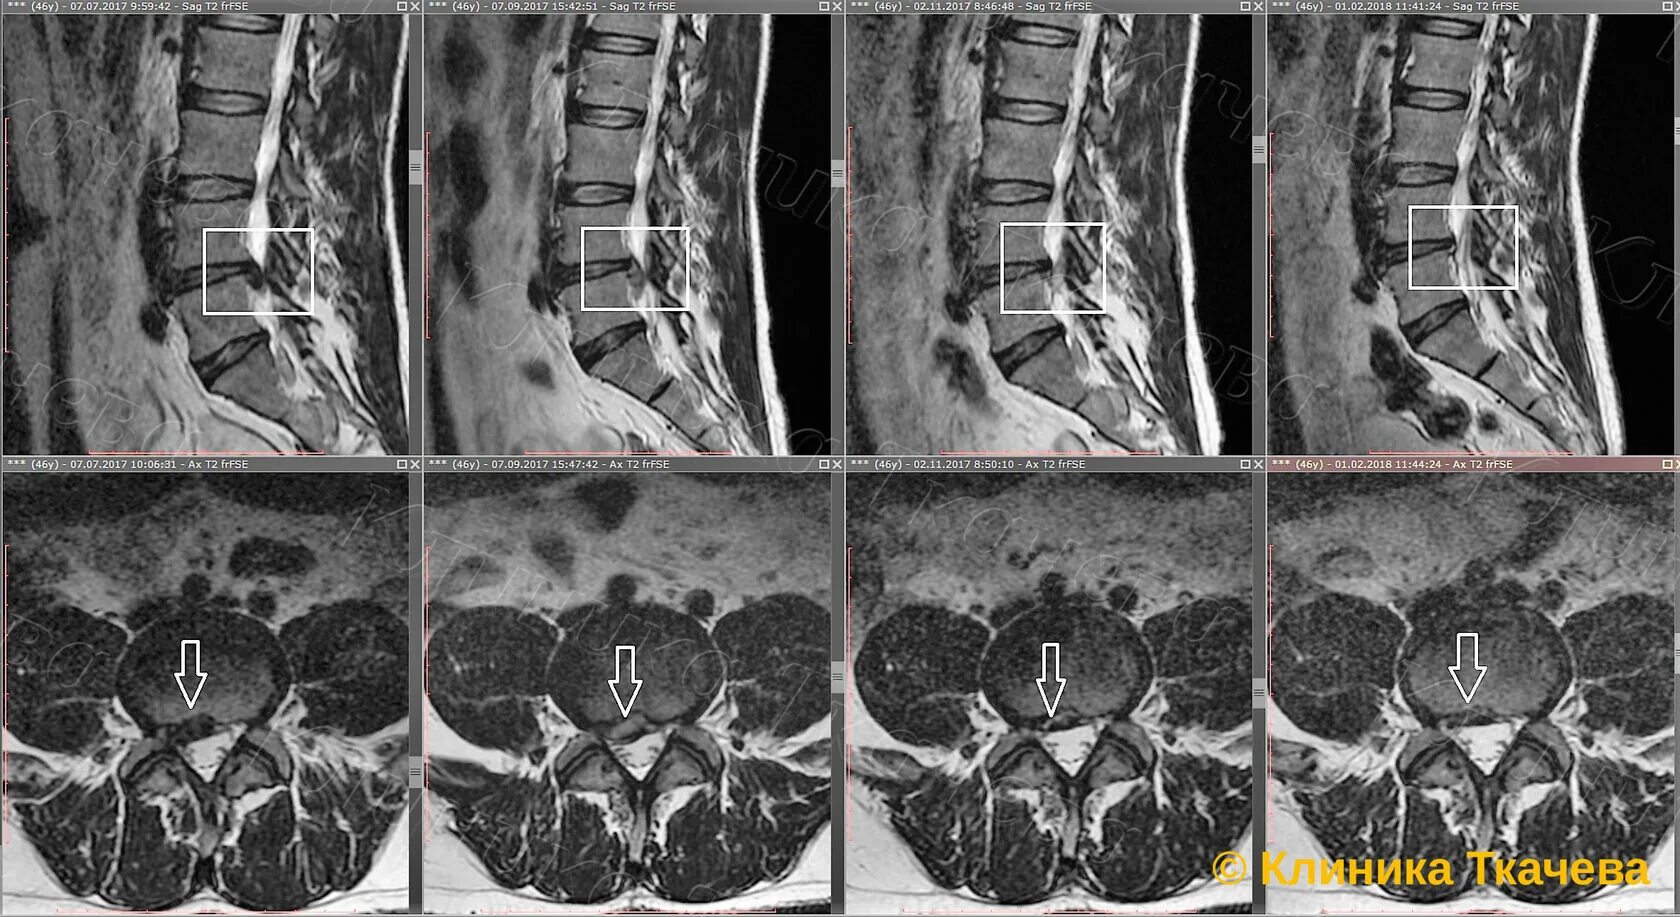

Грыжа диска мрт